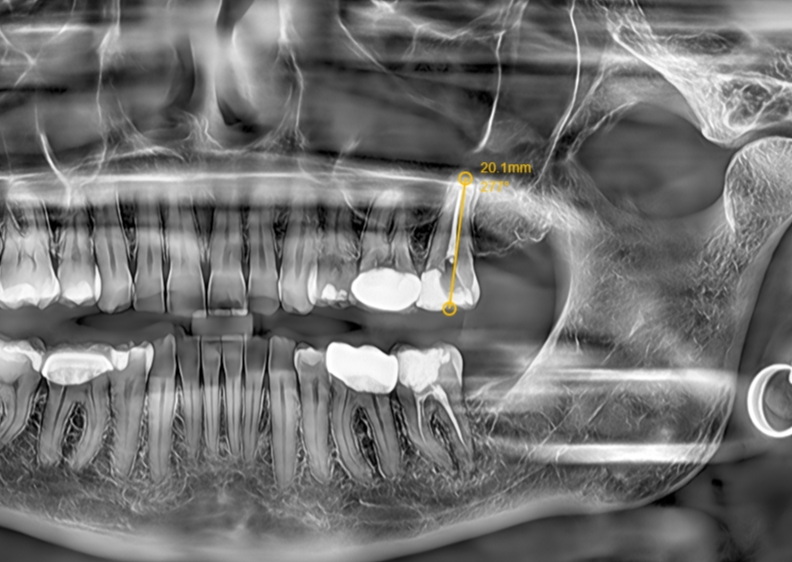

As a specialized masticatory organ, the tooth possesses dual sensory functions: first, the dental pulp nerve located within the pulp cavity, which can accurately perceive external stimuli such as sourness, sweetness, cold, and heat; second, the periodontal ligament surrounding the root surface, which is capable of sensitively detecting masticatory pressure and providing feedback to regulate occlusal force. When the dental pulp becomes infected and develops pulpitis, there is no need for hasty tooth extraction. Root canal therapy (RCT) is the preferred treatment modality for preserving the affected tooth. This procedure thoroughly removes the infected and necrotic pulp tissue, followed by disinfection and obturation of the root canal system, which can effectively eliminate pain and preserve the physiological functions of the tooth. Even though the treated tooth loses the ability to sense temperature and taste stimuli, the periodontal ligament can still normally transmit occlusal force signals, ensuring the fulfillment of masticatory functions. Clinical data indicate that with proper oral hygiene maintenance and necessary coronal restoration, the service life of teeth after root canal therapy can exceed 10 years, and some teeth can even maintain normal function for more than 20 years.

In contrast, dental implant restoration after tooth extraction can restore the masticatory hardness of the tooth, and the implant can form a stable osseointegration with the jawbone. However, dental implants have an inherent physiological limitation—they lack the pressure-sensing mechanism of the periodontal ligament. Patients cannot precisely control the magnitude of occlusal force during mastication; excessive occlusal force is prone to induce peri-implant bone resorption and loosening, ultimately leading to implant failure. In addition, the long-term survival of dental implants is highly dependent on rigorous postoperative maintenance, including professional cleaning care and regular follow-up examinations, making their maintenance significantly more challenging than that of natural teeth after root canal therapy.